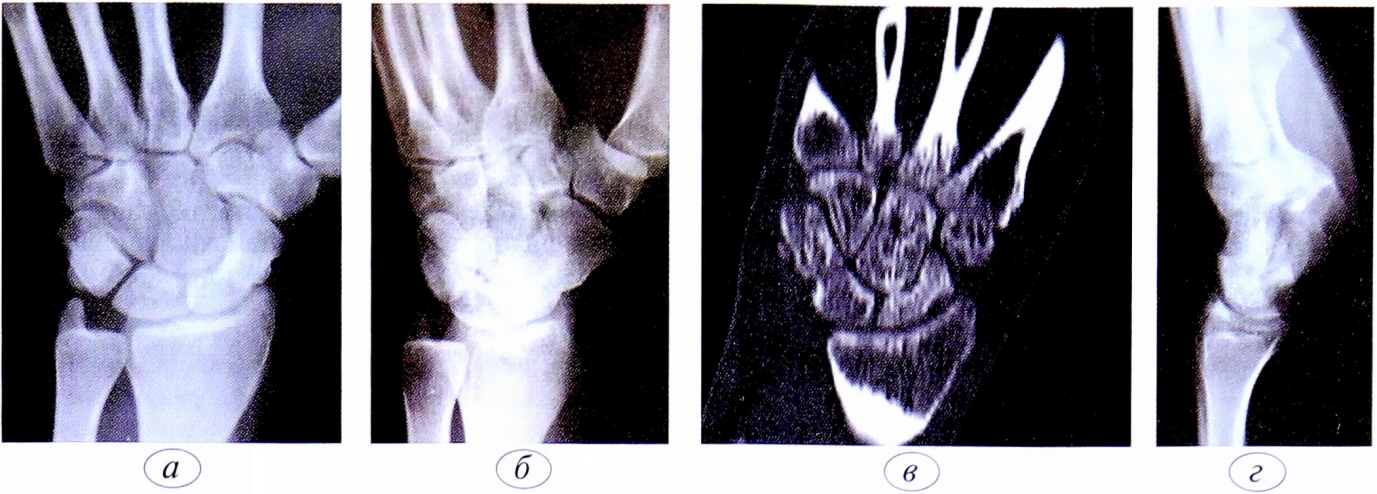

Функция пальцев полная. Сила кулачного схвата правой (доминантной) кисти — 22 кг, снижена почти в 2 раза по сравнению с нормой. Сила схвата левой кисти — 40 кг. Оценка по шкале ВАШ — 3 балла, по опроснику DASH — 21,16 балла. На рентгенограмме (рис. 5, а, б, в) и при компьютерной томографии выявлен ложный сустав ладьевидной кости (см. рис. 6, г).

Рис. 6. Пациент К.,19 лет. Диагноз: ложный сустав ладьевидной кости правой кисти. а — рентгенограмма в прямой проекции; б — рентгенограмма в ¾; в — рентгенограмма в боковой проекции; г — компьютерная томография.

Fig. 6. Patient К.,19 years. Diagnosis: pseudarthrosis of the scaphoid of the right hand. a — straight projection x-ray; b — ¾ projection x-ray; c — lateral projection x-ray; d — computed tomography.